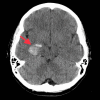

Figure 1

Figure 1. Intraparenchymal bleed in the medial right temporal lobe measuring 2.2 cm in diameter without midline shift